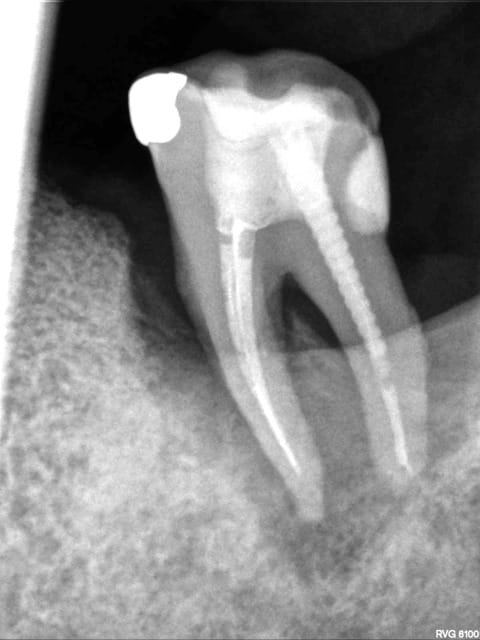

R71 est de cette semaine, allez y comprendre quelque chose, dame nature a été très gentille sur ce coup là, de l'os s'est reformé.

Une explication à me proposer?

R69 qeompc - Eugenol

R71 yby2cf - Eugenol

Index vakr2r - Eugenol

Pour info j'ai eu à un moment lésion endo paro le sondage en mésial indiquait une communication jusqu'à l'apex. et le tout début c'était pulpite allant vers nécrose compliquée d'atteinte paro sur vieux stellite pas mis, depuis endo après Ca(OH)2 et ABT, surfaçage et det régulier, nouveau stellite adapté. Puis flambée avec envie du patient d'extrac, commande de dent résine pour adjonction, le jour J plus de douleur, demande du patient de garder la dent encore un peu, et là, la dernière rx la semaine dernière gain d'os après une situation qui prônait bien l'avulsion!

Ce qui correspond a une infection du a une cause local transitoire, une fois l'évenenment passé vue que la situation clinique était saine, l'os c'est reformé. IL y a 6 mois entre les deux dernière radio non ?

Oui il y a 6 mois entre le 2 derniers clichés, mais il est bien à noter que depuis le début et jusqu'en mai cela n'avait fait qu'empirer, or l'endo est beaucoup plus ancienne ; d'où ma surprise de voir un regain alors que tous les signes étaient à la dégradation depuis des mois, ce qui me fait dire que la flambée n'était pas un phénomène épisodique mais bien un soucis latent ce que la clinique indiquait pendant des mois (infla+ mobi+ de temps à autre douleurs). donc je reste sans explication.

Quant à l'histoire des 4 murs je veux bien mais d'autres cas sur lesquels j'ai porté de grands efforts d'assainissement n'ont pas donné de reconstruction avec réattache, je n'y crois donc pas dans de pareil proportion de perte osseuse.

L'angulation est différente, et pour preuve sur la R71 on voit bien les deux canaux mésiaux de manière distincte, alors qu'ils étaient toujours confondus sur les autres radio...

Il n'y a jamais de "miracle" en paro! Pour une lésion endo oui, mais pas pour une lésion paro...